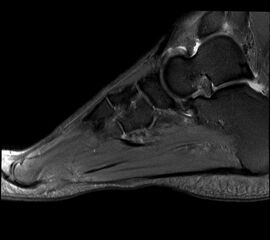

Abbildung 6: Darstellung des Baxter Nerven im MRT (siehe Pfeil)

Zum Lesen der Bildbeschreibung und zur Vollansicht bitte das Bild anklicken. Bild: Manfred Thomas.